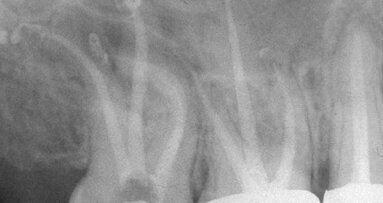

The “unknown worry,” the “elephant in the access cavity” that few are aware of and hardly anybody talks about, is the apical laceration that commonly occurs during rotary shaping procedures. The reason such a big problem is spoken of so little, is that when apical laceration during rotary shaping (alders) occurs, the only evidence of the disastrous shaping outcome is the inevitable overfill that follows — a result seldom attributed to its true etiology but most commonly identified as a cone fit or condensation failure.

When a given file design always cut to length, it is highly unlikely to exhibit fidelity to the original canal path in apically curved canals. Combining that fact with the fact that at least half of all canal curvatures are hidden in our conventional radiographic imaging, makes an incontrovertible case for safety above cutting efficiency if only one of these two attributes is designed into an instrument set.